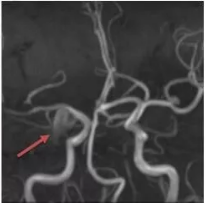

① 磁共振下MRA脑血管成像

② 脑动脉瘤